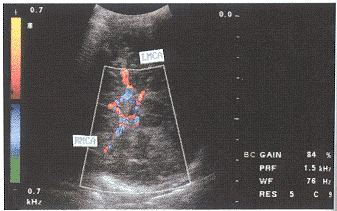

MCA、PCA的血流测定:从颞侧作水平扫查,此时超声声束与血管夹角较小。取样容积放在主干进行取样。显示大脑动脉环,探查MCA、PCA。彩色多普勒显示,大脑环动脉环上方,及下方分别可见左右两侧的彩色血流(图3、4)。左侧探测,左侧MCA、PCA呈红色血流,多普勒频谱为正向,右侧MCA、PCA呈蓝色血流。大脑后动脉,位于Will环后方,左侧呈红色血流,右侧呈蓝色血流,多普勒频谱为负向。探头改变方向,血流及频谱则反之(图5、6)。

图5 RMCA多普勒频谱

图6 LPCA多普勒频谱